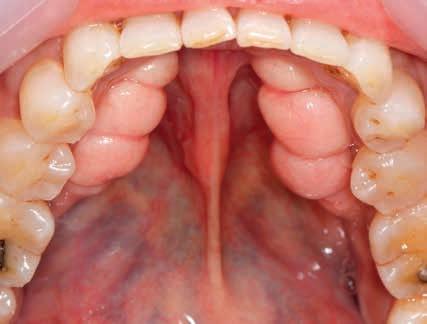

Patienttilfælde 1 (Fig. 1) er en 37-årig kvinde, henvist efter succesfuld behandling af stadie 3-parodontitis. Der er nu sundt

Før behandling

parodontium, ingen pocher over 4 mm, og både blødnings- og plakindeks er under 10 %. Patienten er motiveret for ortodontisk behandling, da hendes tænder er vandret over tid, delvist som følge af reduceret parodontium.

Der ses anterior trangstilling i begge kæber og overerupterede 1+1 og 2,1-1,2, hvilket resulterer i dybt bid med 2- tæt på ganepåbidning. Der er normale sidetandsrelationer, men der ses 5 mm horisontalt overbid (HOB) og 7 mm vertikalt

overbid (VOB). Papillen mellem 1+1 er betydeligt reduceret pga. fæstetab, og de mesialt kippede 1+1 har resulteret i en ”dark triangle”. Den facioorale funktion er for nuværende i.a. Panoramarøntgen (Fig. 1, I) viser marginalt knogletab i begge kæber og fravær af 8,7+7,8 og 8,7-8.

Objektivt anbefales behandling af det dybe bid, som ubehandlet forventes at forværres yderligere over tid. Patienten har ønske om behandling med æstetisk ortodontisk apparatur, alignere, og det vurderes muligt at behandle malokklusionen med alignere. Dog anbefales det generelt, at alignere undgås eller benyttes med væsentlige modifikationer af alignerens retention ved tandmobilitet, da dette ellers kan medføre jiggling, når aligneren tages af og på mange gange dagligt. På den anden side er der nogen evidens for, at alignerbehandling er associeret med bedre renhold og parodontal sundhed sammenlignet med fast apparatur (16).